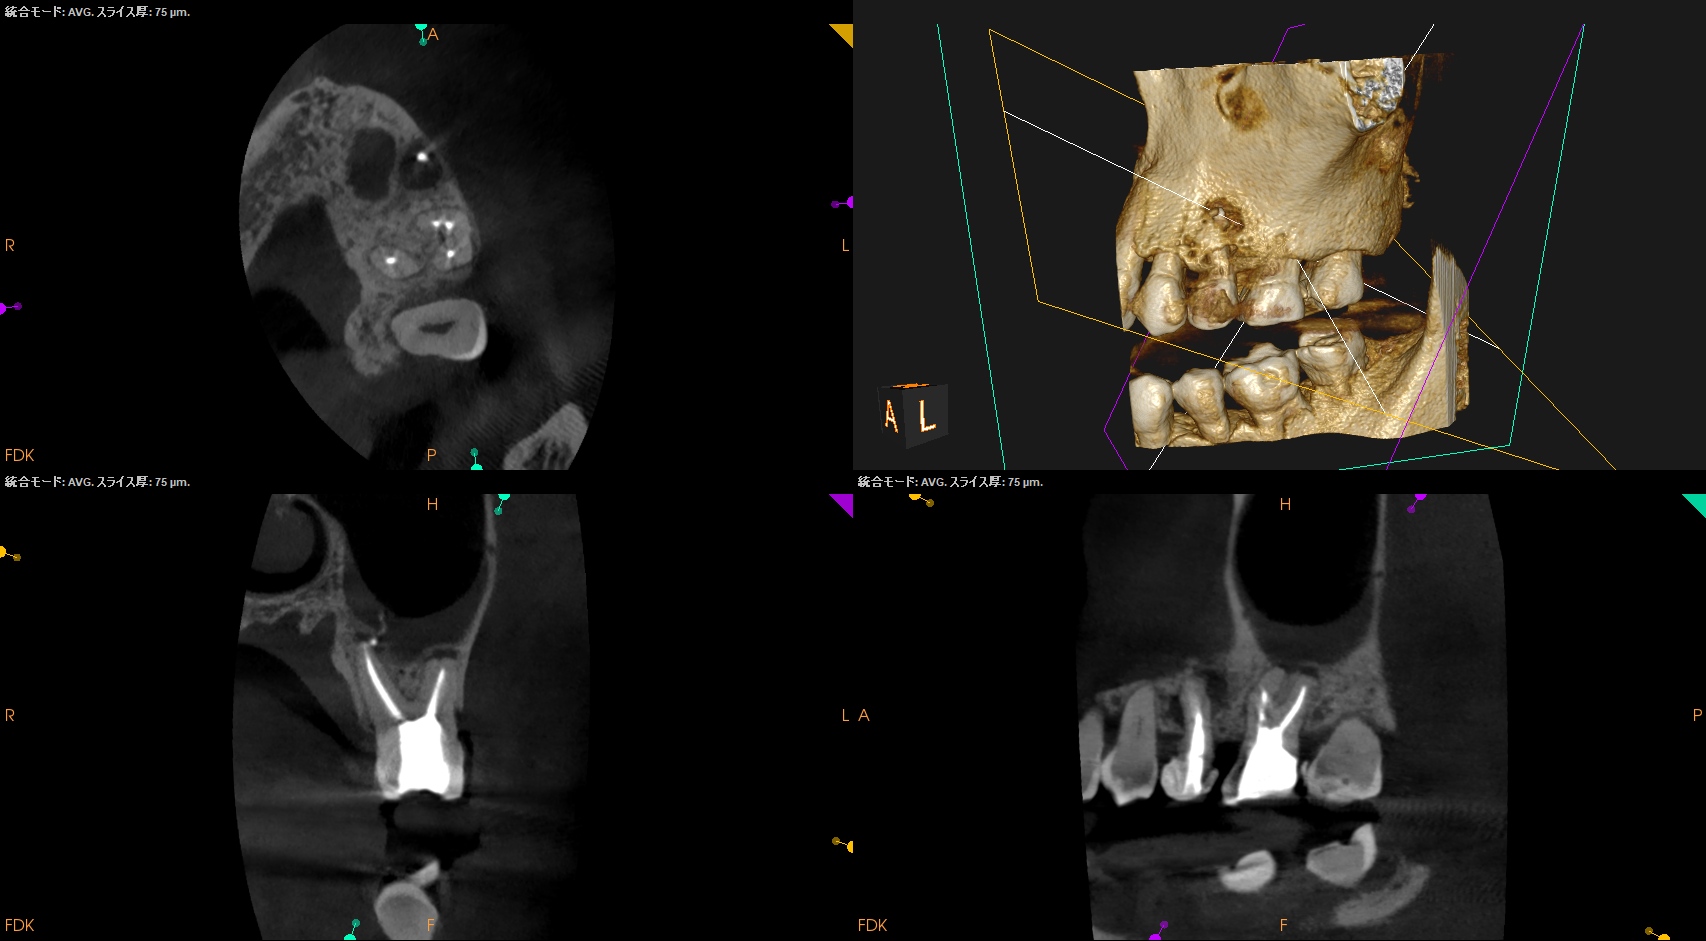

CBCTも撮影した。

これはマストの医療行為である、と私からは告げておこう。

#14

MB

MB2

DB

P

B

ヨシダ社のパノラマと前述のパノラマを比較してほしい。

話にならないくらい、どちらが優れた画質であるか?ということを。

さておき、#13にも病変があるのがわかるので#13も分析した。